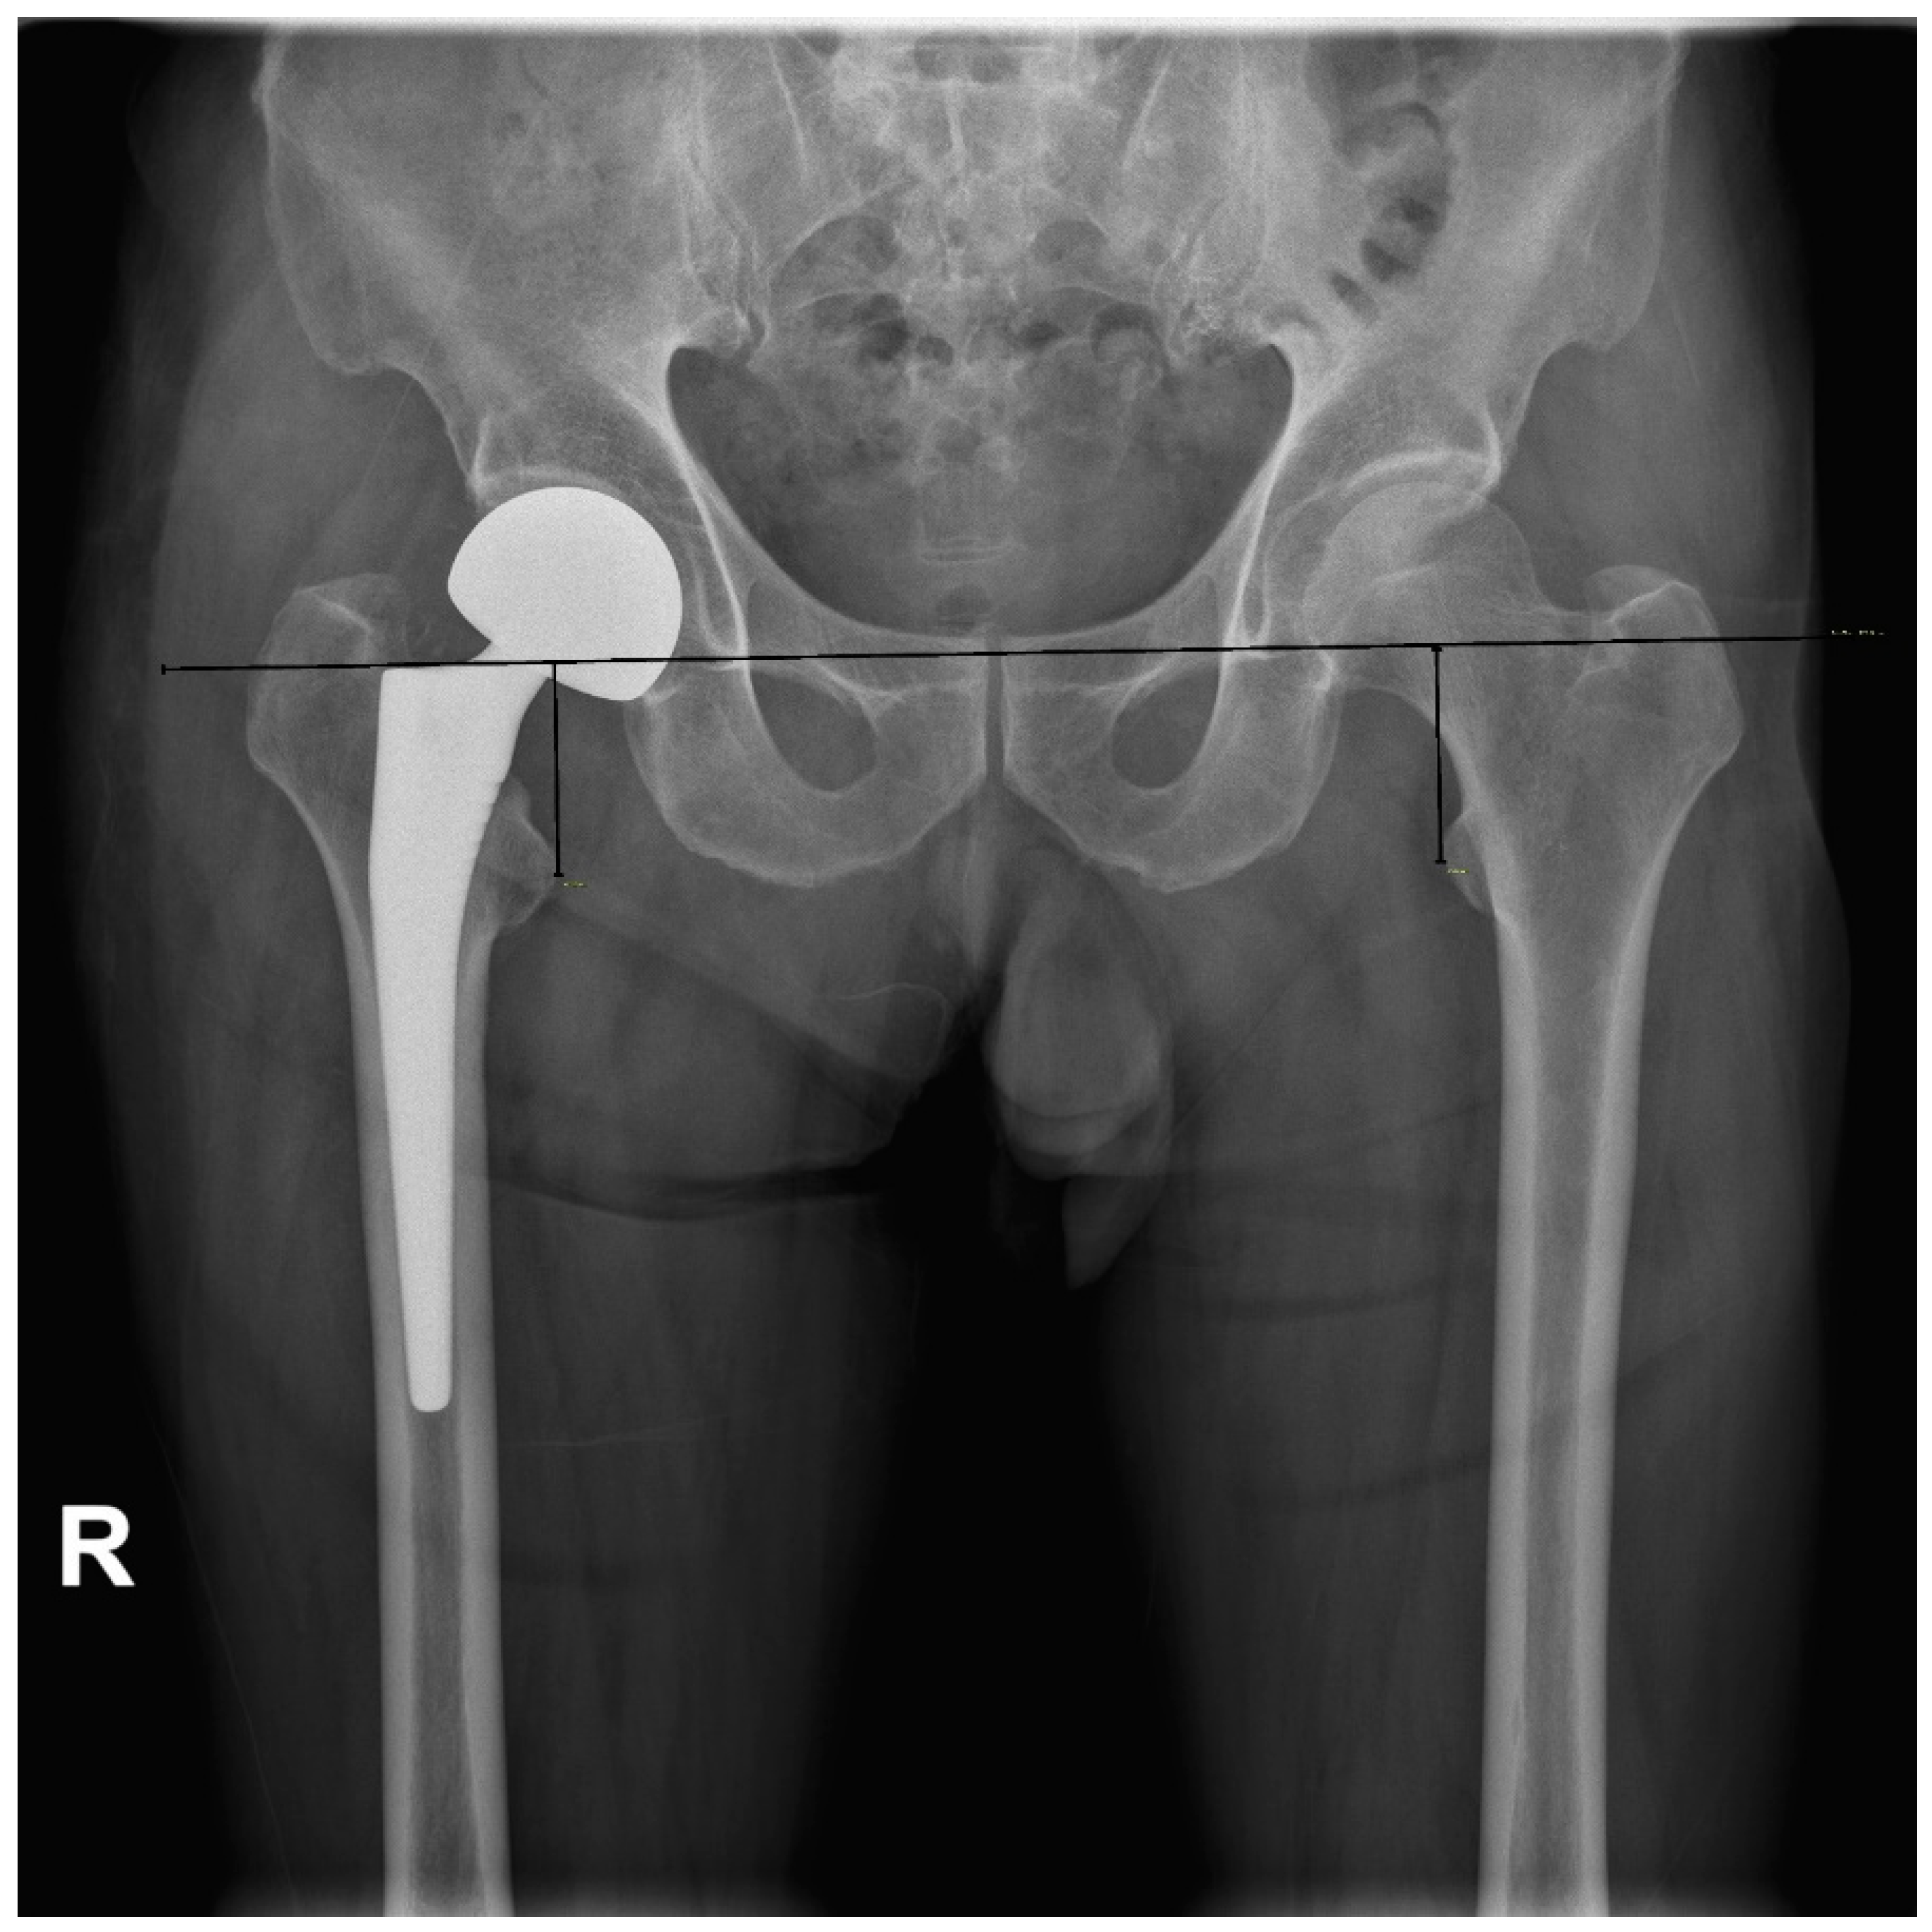

2.2. Radiologic Parameters

- Matsuda, K.; Nakamura, S.; Matsushita, T. A simple method to minimize limb-length discrepancy after hip arthroplasty. Acta Orthop. 2006, 77, 375–379. [Google Scholar] [CrossRef]

- Lim, Y.W.; Chang, Y.J.; Kwon, S.Y.; Kim, Y.S. A simple method using a PACS to minimize leg length discrepancy in primary THA: A method to minimize leg length discrepancy. J. Arthroplast. 2013, 28, 1791–1795. [Google Scholar] [CrossRef]

- Kim, S.C.; Lim, Y.W.; Kwon, S.Y.; Lee, J.K.; Park, I.K.; Kim, Y.S. Comparative Analysis of Radiographic Hip Joint Geometry Using Measurement Tools on Picture Archiving and Communication System: A Prospective Study of 100 Pelvic Radiographs of Koreans. J. Arthroplast. 2016, 31, 2597–2602. [Google Scholar] [CrossRef]

| Gonzalez et al. (2005) [16] | 1.71 | Measuring between the proximal edge of the lesser trochanter and the center of rotation of the femoral head (HLD) |

| Matsuda (2006) [17] | 2.0 | Measuring the actual HLD preoperatively and reproducing it in the operative field with a modular neck system |

| Lim et al. (2013) [18] | 1.5 | Measuring head to lesser trochanter length using PACS and reproducing it in the operative field with a modular neck system |

| Wang et al. (2019) [42] | 4.4 | Measuring ratio of contralateral femoral head and the distance of HLD using PACS |